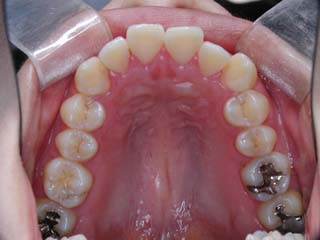

使用した主な装置名:TPB、マルチブラケット装置、オーソアンカー SMAPシステム

一般的なマルチブラケット装置を用いた治療では、先ずは形状記憶合金のワイヤーで大まかに配列を行い、バネをきかせたワイヤー、堅いワイヤーを使って仕上げていく方法です。

最終仕上げの段階です。かなり太めのワイヤーが入っていますが、このワイヤーの後にオーバーコレクション(元々の歯の捻れが有った場合、後戻りで出てきやすいので、わざと過剰に捻れを治しておく事)を行うための、細めのワイヤーを使う事もあります。